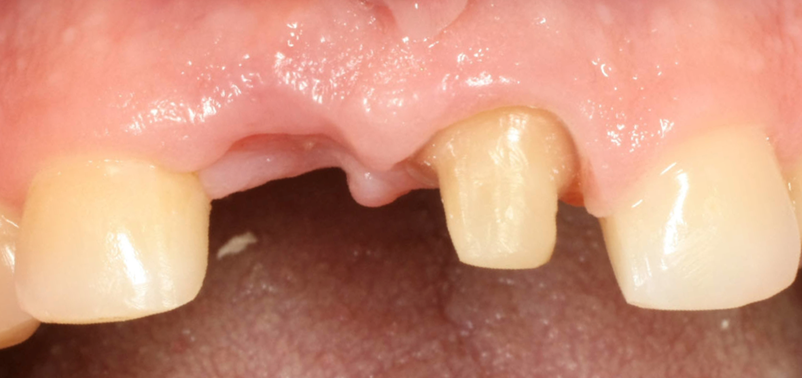

Immagine clinica iniziale ed evidenza radiografica del riassorbimento radicolare

Evidenza clinica della mancanza di parete vestibolare